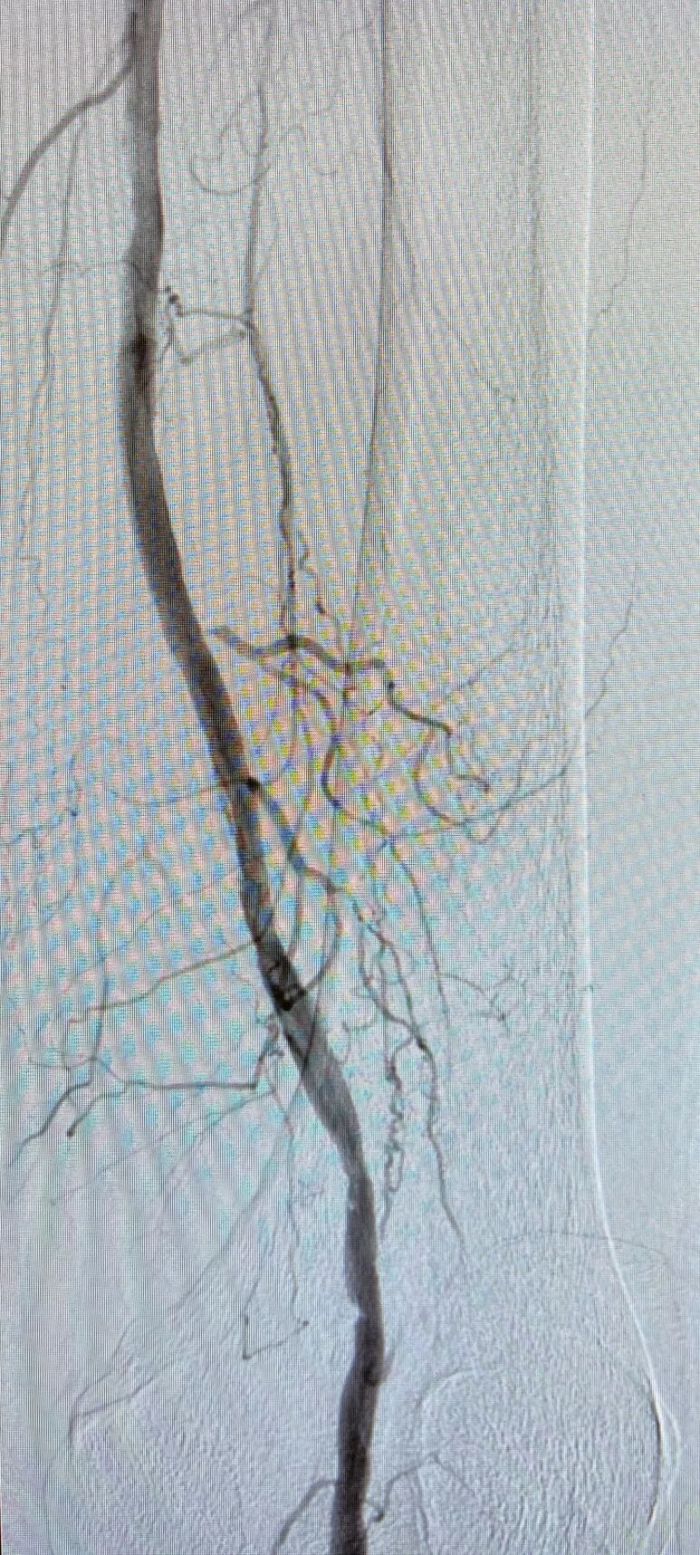

术前闭塞的腘动脉远端几无血流

球囊扩张后血管恢复通畅